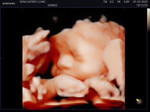

มีใคร อัลตราซาวด์ 4Dตอน 20 วีคแล้วบ้างคะ ตื่นเต้นมากเลยค่ะเริ่มเห็นหน้าลูกชัดๆบ้างแล้ว

อันนี้ซาวด์ตอน 17wจะ18wค่ะ เเม่บ้านนี้รอไปซาวด์อีกทีช่วงเกือบๆ6-7เดือนค่ะ จะได้เห็น น้องได้ชัดๆ ไปหลายรอบพ่อบ้านนี้บ่นค่ะ เพราะเเพง😆บอกให้เก็บเงิน ซื้อของให้ลูกดีกว่า